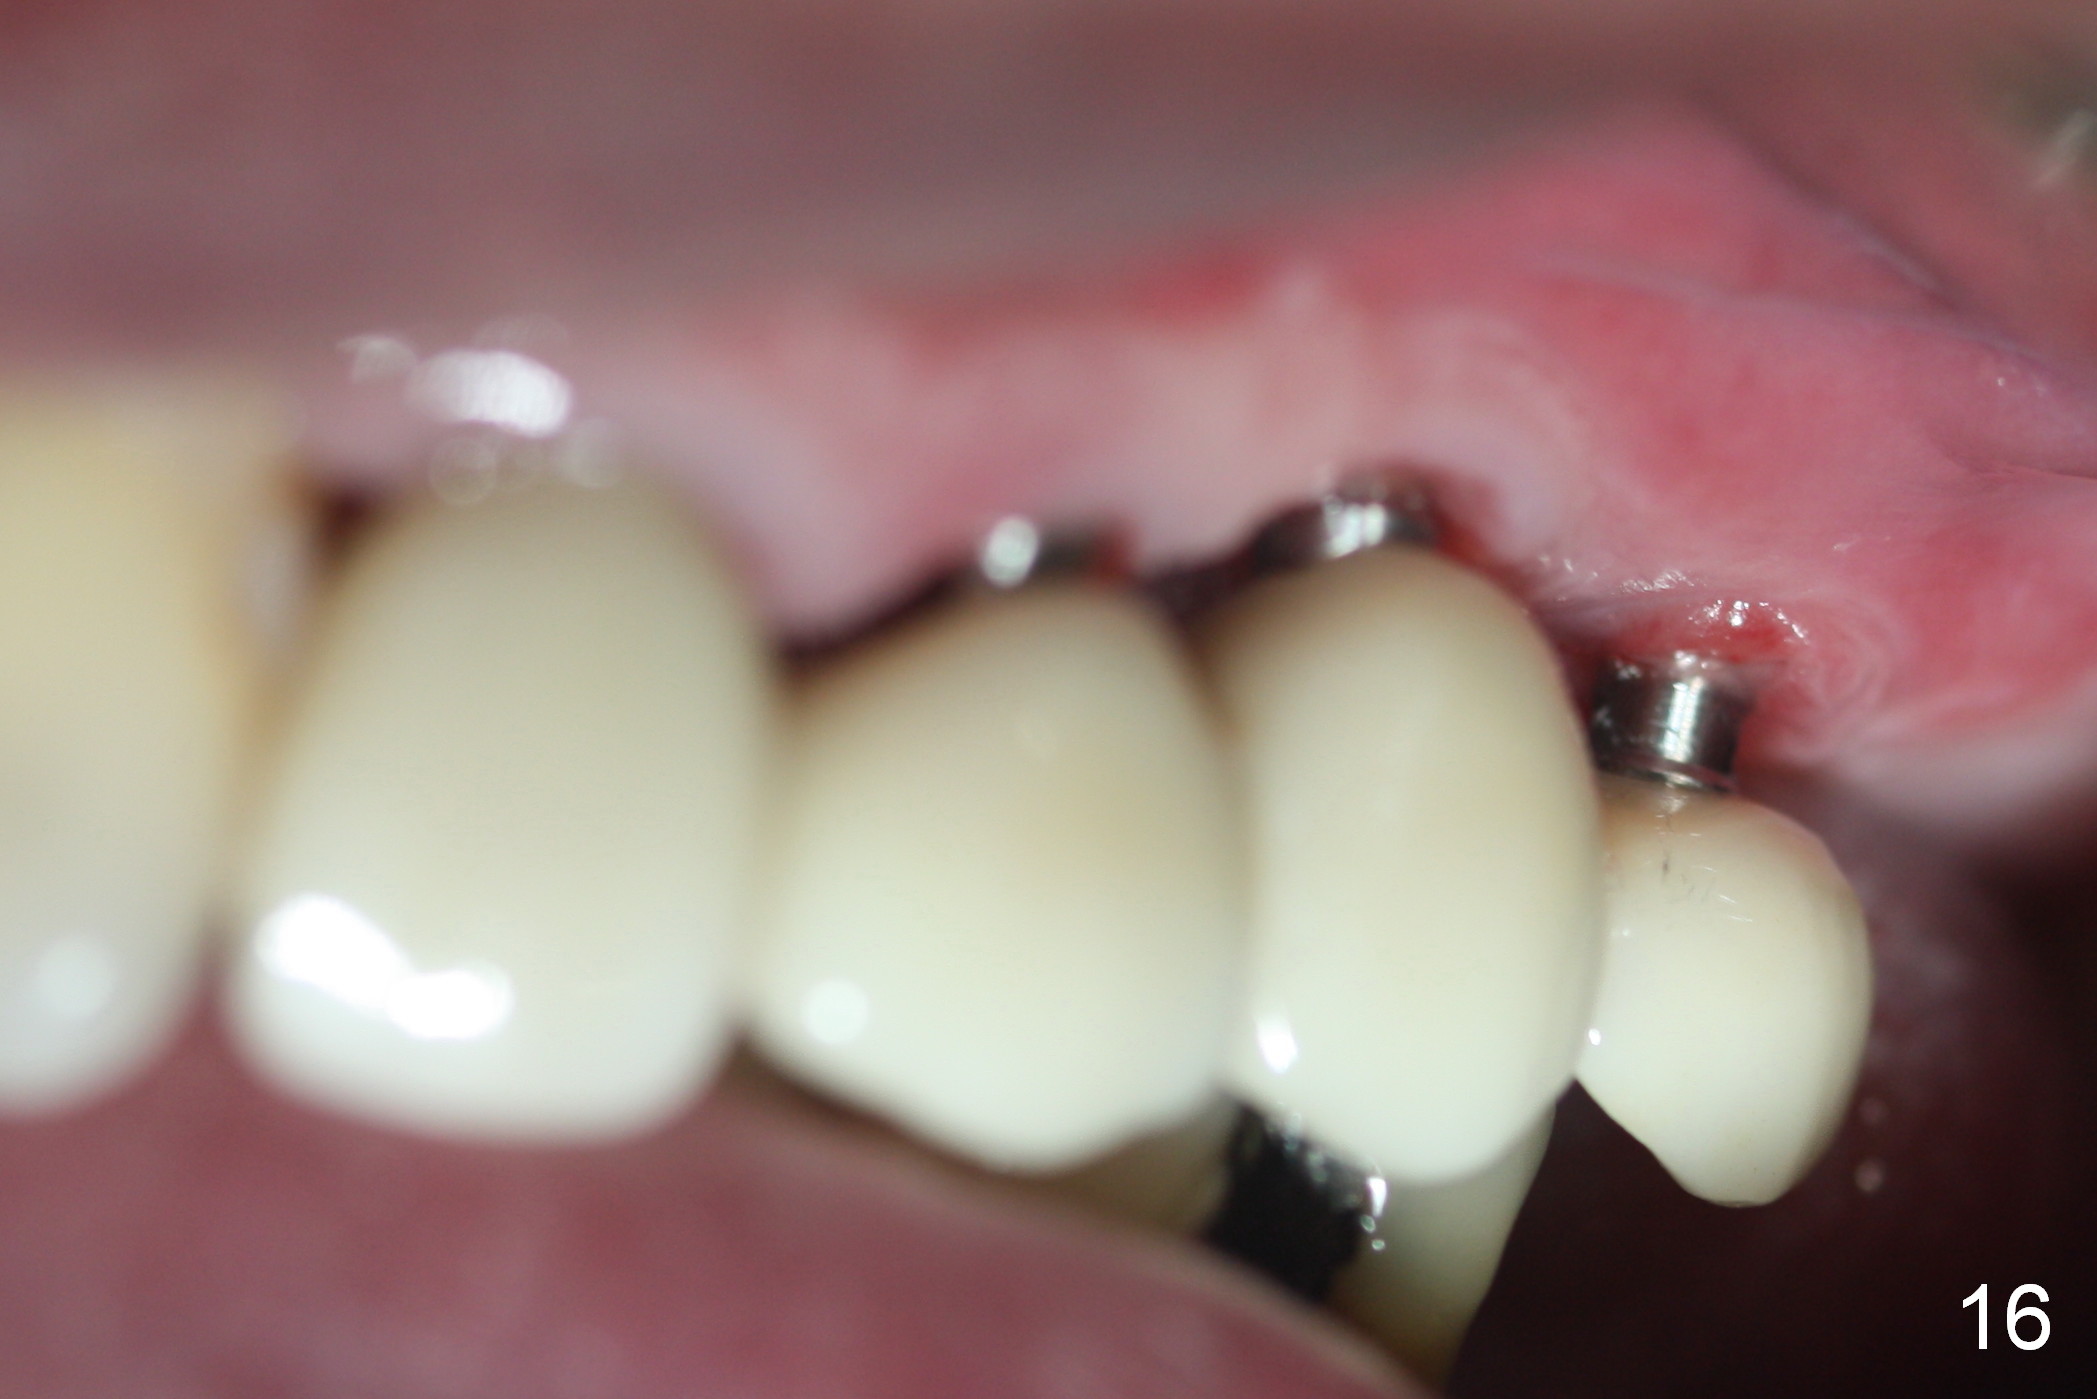

At the time of cementation, the crowns at #11-13 do not contact the gingiva (Fig.16).  One month post cementation, the gingiva appears to have grown coronally (Fig.17).